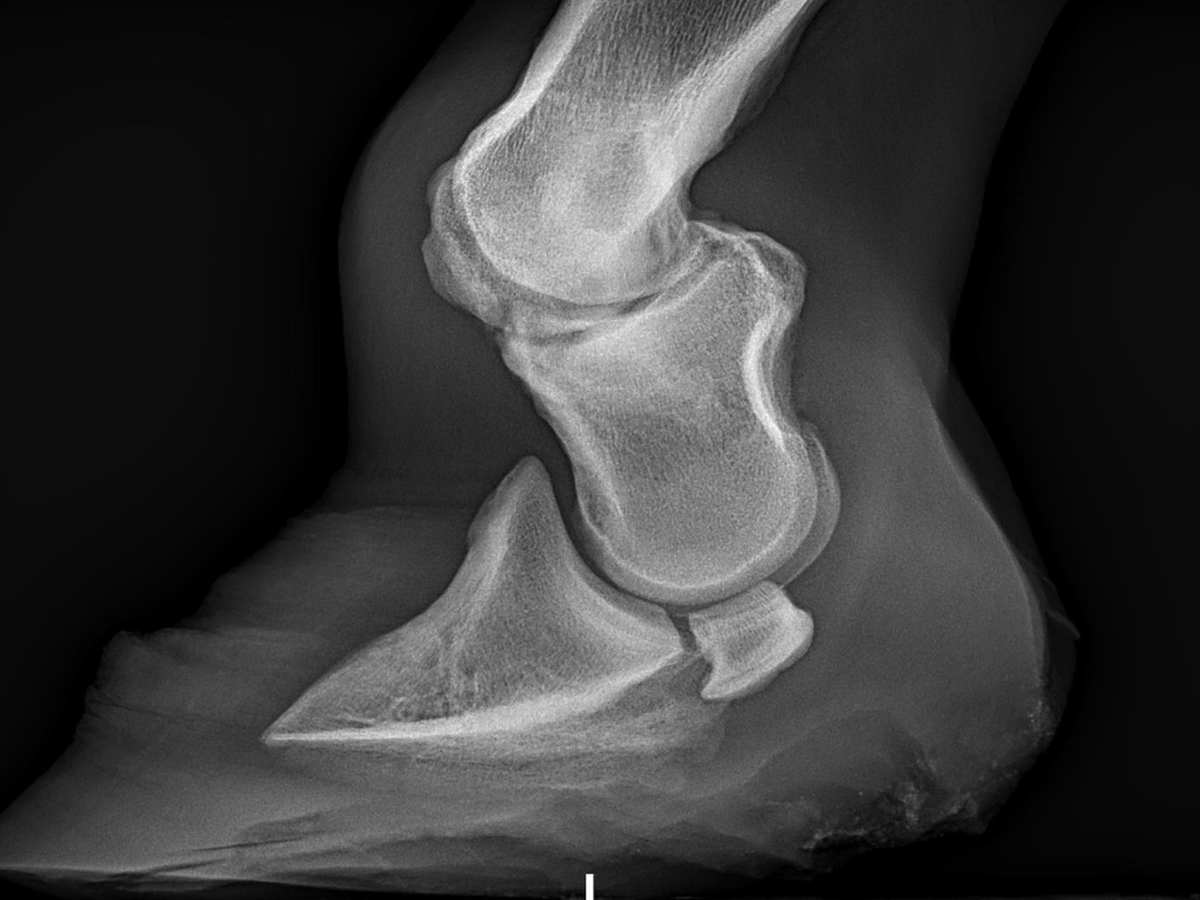

This is Phin my 11 month old colt i got from a slaughter holding pen in New York. He has a lige threatening bone deformity that needs operated on immediately. His date of surgery is December 18th and i got informed last week. After countless hours of phone calls with loan companies and banks this is my last resort. I have to pay close to half of the surgery cost upfront on the day of drop off. (12/17) this gave me no time to save or prepare. If any friends or family want to help me out i would be so great-full. Since christmas is right around the corner i know money is tight. But if you are friends or family this would be an amazing christmas gift for me.